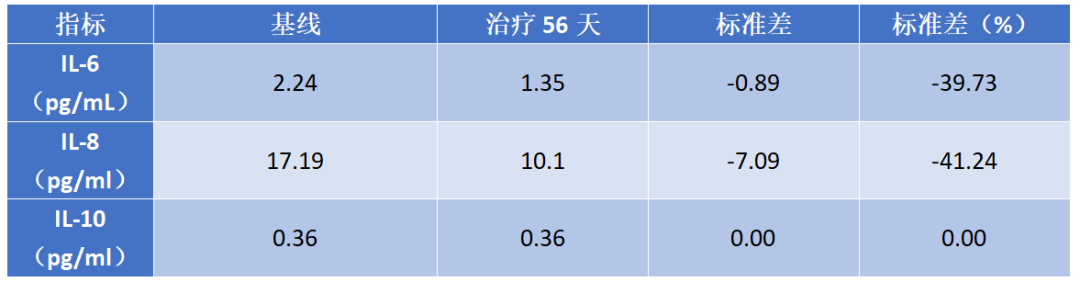

3. IL-6、IL-8和IL-10变化

用药后IL-6和IL-8下降明显,详见图3。

图3. IL-6、IL-8和IL-10水平变化